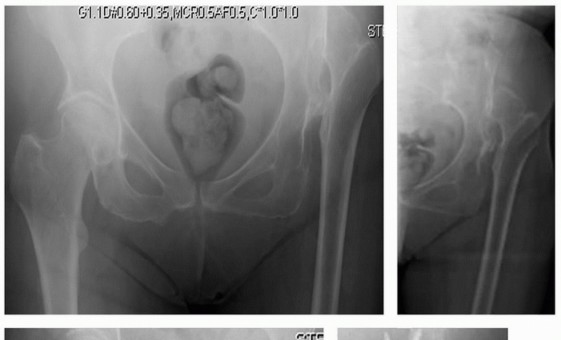

يُعد خلع الورك التنموي (Developmental Dysplasia of the Hip - DDH) حالة معقدة تؤثر على مفصل الورك، وتتطلب غالبًا تدخلات جراحية متقدمة لاستعادة وظيفته وتخفيف الألم. في الحالات الشديدة والمزمنة التي تصيب البالغين، يصبح استبدال مفصل الورك الكلي (Total Hip Replacement - THR) خيارًا حتميًا، لكن التشوهات التشريحية المصاحبة لـ DDH تجعل هذا الإجراء تحديًا استثنائيًا. هنا تبرز أهمية تقنية "ترقيع رأس الفخذ الذاتي"، وهي طريقة جراحية مبتكرة يستخدم فيها عظم رأس الفخذ الخاص بالمريض، والذي يتم استئصاله عادةً أثناء الجراحة، لتعزيز التجويف الحقي (الحُق) الضحل أو المتشوه. هذا النهج لا يوفر قاعدة عظمية قوية ومستقرة للمفصل الصناعي فحسب، بل يقلل أيضًا من مخاطر الرفض أو العدوى المرتبطة بالطعوم الاصطناعية، ويساعد في استعادة مركز دوران الورك الطبيعي، مما يقلل من تفاوت طول الساقين ويحسن الميكانيكا الحيوية للمفصل.

يُعد خلع الورك التنموي (Developmental Dysplasia of the Hip - DDH) حالة تؤثر على مفصل الورك، حيث لا يتطور التجويف الحقي (الحُق) ورأس عظم الفخذ بشكل صحيح، مما يؤدي إلى عدم استقرار المفصل أو خلع جزئي أو كلي. يمكن أن تتراوح شدة هذه الحالة من خلل بسيط في تطور المفصل إلى خلع كامل ومزمن، مما يسبب الألم، صعوبة في الحركة، وتفاوتًا ملحوظًا في طول الساقين، ويؤثر بشكل كبير على جودة حياة المريض وقدرته على ممارسة الأنشطة اليومية. مع مرور الوقت، يمكن أن تتطور هذه الحالة إلى التهاب مفصل الورك التنكسي (Osteoarthritis) في سن مبكرة، مما يزيد من معاناة المريض ويحد من حركته.

في حالات DDH، لا يتطور مفصل الورك بشكل صحيح، مما يؤدي إلى تشوهات هيكلية تؤثر على استقراره ووظيفته. تشمل هذه التشوهات:

* التجويف الحقي الضحل (Shallow Acetabulum): بدلاً من أن يكون عميقًا وكرويًا، يكون التجويف الحقي مسطحًا أو ضحلًا، مما لا يوفر تغطية كافية لرأس الفخذ.

* نقص التغطية العظمية: يكون جزء كبير من رأس الفخذ خارج التجويف الحقي، مما يزيد من الضغط على حواف التجويف ويؤدي إلى تآكل مبكر.

* تغير مركز دوران الورك: يتحرك مركز المفصل إلى الأعلى والخلف، مما يغير الميكانيكا الحيوية للمشي ويزيد الضغط على المفاصل الأخرى.

هذه التشوهات تجعل المفصل عرضة للخلع الجزئي أو الكلي، وتؤدي إلى تطور التهاب المفاصل التنكسي مبكرًا.